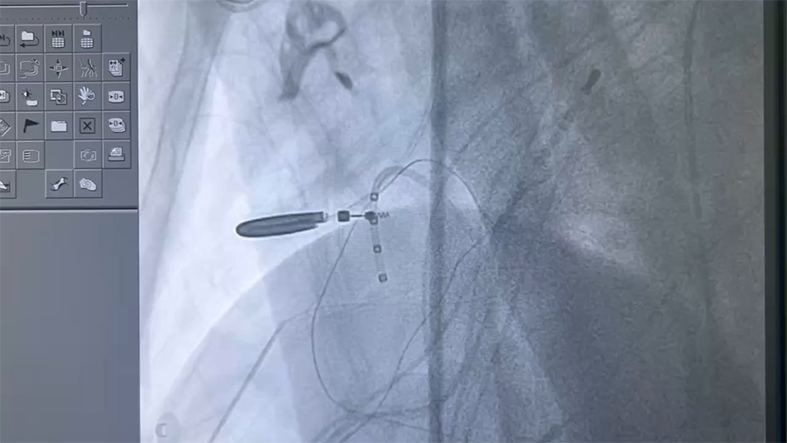

山西盈康一生总医院心律失常科马瑞芳主任团队接诊后,针对张先生病情开展多次MDT讨论,制定出一套严密的手术方案。为保障手术安全,特别邀请中国医学科学院阜外医院心内科专家刘俊做技术指导。10月13日,马瑞芳主任团队在介入导管室为张先生进行了干性心包穿刺、心内膜联合心外膜消融,经过4个小时全力奋战,消融结果满意,且术后反复进行刺激,均未诱发室速发作。目前,患者已平安出院。

ARVC相关的室速消融难度极大,大多数需要心内膜联合心外膜消融才能取得更高的成功率,但是心外膜消融为非常规消融技术,需要干性穿刺心包进行心外膜消融。山西盈康一生总医院(运城第一医院)顺利完成这一高难度手术,是医院在器质性心脏病复杂心律失常诊治水平的又一重大进步。